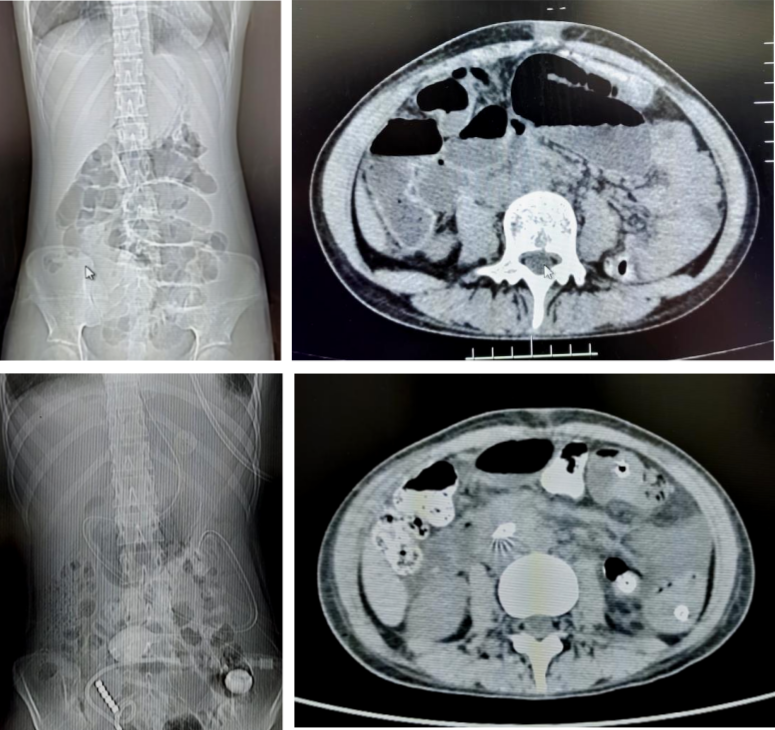

病例1

71岁的患者刘先生,因行膀胱癌根治术、回肠代膀胱术出现肠梗阻。后在我院放射介入室行DSA引导下经鼻肠梗阻导管置入术,术后当日患者腹胀较前明显缓解,术后第6天患者排气、排便,肠管恢复通畅,拔除肠梗阻导管。

病例2

18岁的患者叶女士,因行阑尾穿孔导致盆腔脓肿后出现肠梗阻。后在我院放射介入室行DSA引导下经鼻肠梗阻导管置入术,术后当日患者腹胀较前明显缓解,术后第3天患者排气、排便,肠管恢复通畅,拔除肠梗阻导管。